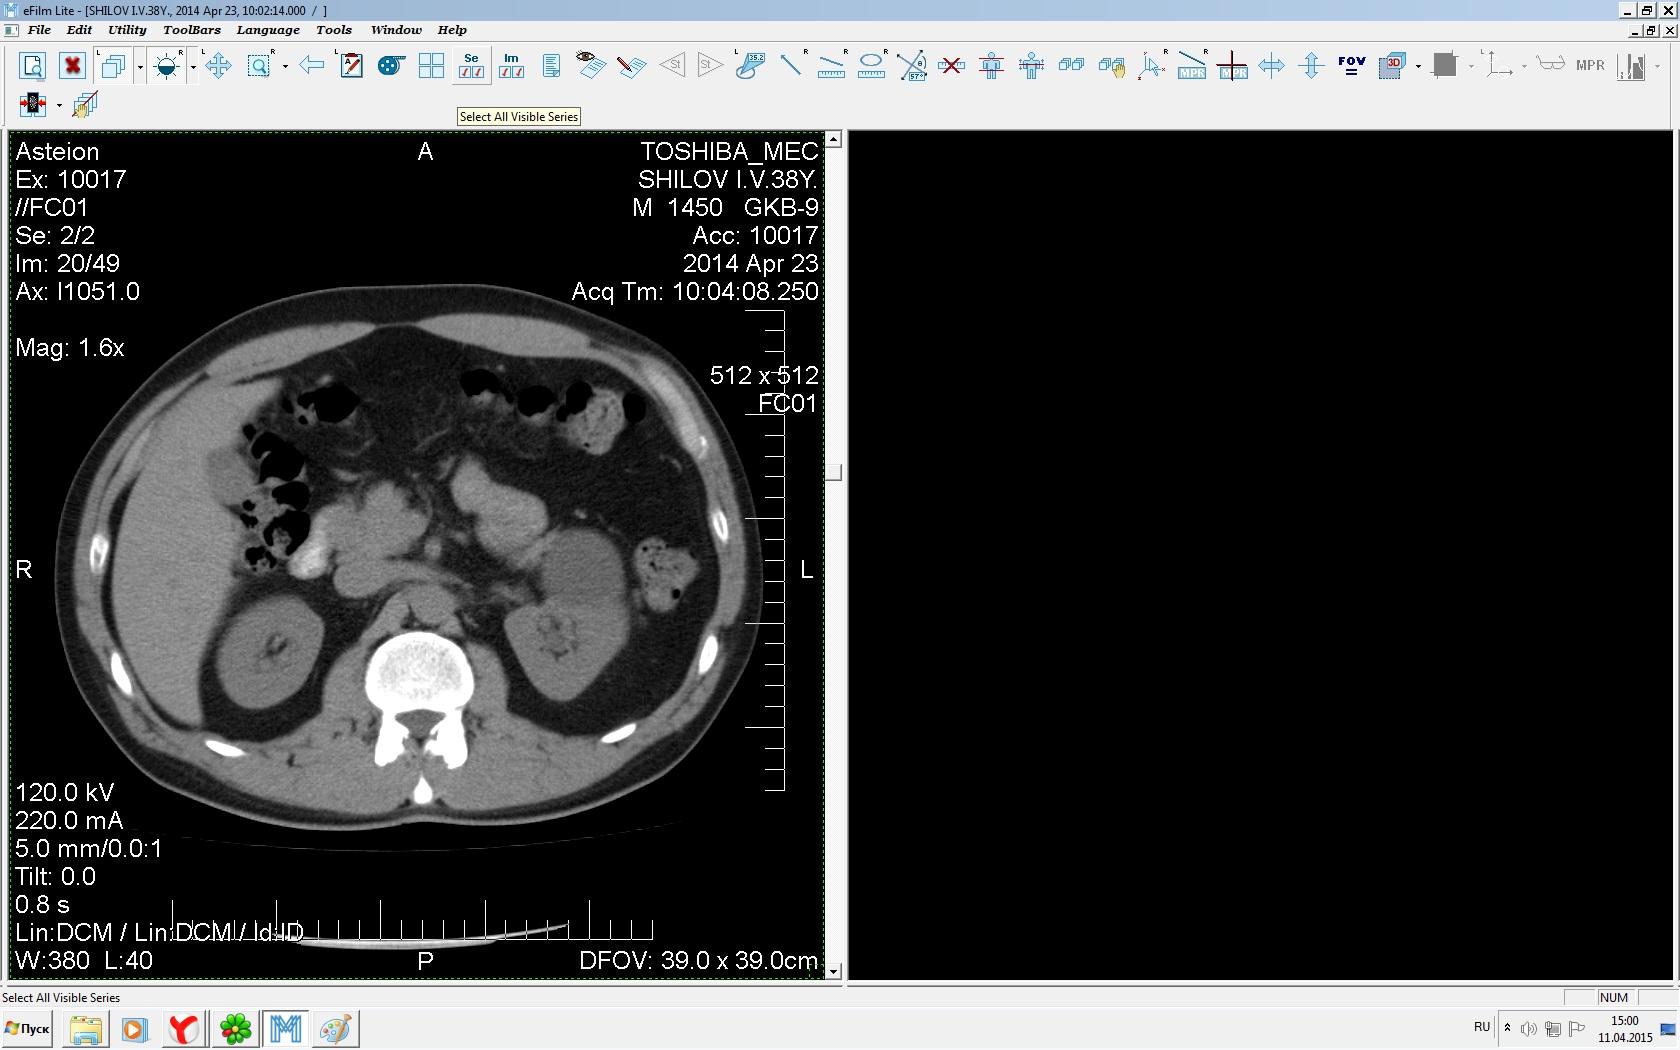

Здравствуйте. У меня киста левой почки. Из заключения: левая почка увеличена, деформирована за счёт наличия в среднем сегменте округлого жидкостного +6, +15 HU образования 66х53 мм, деформирует, поддавливает чаше-лоханочную систему. Сосудистые ножки структурные. В урологии мне сперва предложили лапароскопию, когда я лёг на операцию - изменили на полостную в связи со сложностью. Потом сказали что шансов вырезать кисту без почки практически нет. Даже если кисту удалить чудесным способом, то почка всё равно сложится и не будет работать. В итоге операцию отменили. Скажите, пожалуйста, есть ли современный метод удалить кисту и сохранить почку в моём случае? Томография почки в приложениях. Заранее благодарю.

Эту кисту можно просто пропунктировать, аспирировать и склерозировать - под местной анестезией. Ничего сверхестетственного не определяется по данным КТ. Можете написать мне на почту. aristova-tatyana@mail.ru